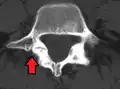

X-ray of measurement of spondylolisthesis at the lumbosacral joint, being 25% (grade 1) in this example -

X-ray picture of a grade 1 isthmic anterolisthesis at L4-5 -

MRI of L5-S1 anterolisthesis -

X-ray of a grade 4 anterolisthesis at L5-S1 with spinal misalignment indicated